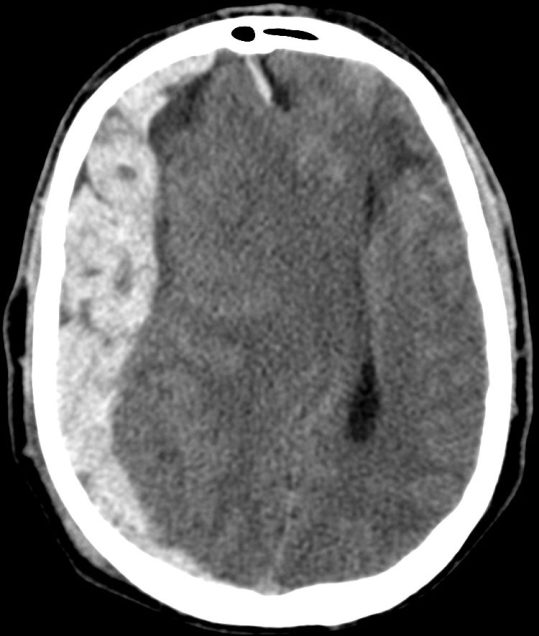

Hematoma Subdural.

- Se localiza entre la duramadre y la aracnoides y suele ser de origen venoso por la disrupción de venas corticales.

- Puede localizarse en punto de golpe y también en el de contragolpe.

- Semiluna hiperdensa (si agudo). Localización: Convexidad > hoz > tentorio

- Cuando son subagudos pasan a ser Isodensos, se identifican porque hay separación del cortex respecto a la tabla interna y efecto masa sin «masa aparente»: colpaso ventricular, desplazamiento de la línea media, etc.

- En estadío crónico puede ser hipodensos.

- Puede cruzar suturas.

- Puede asociar fracturas, contusiones, efecto masas, edema cerebral, HSA.